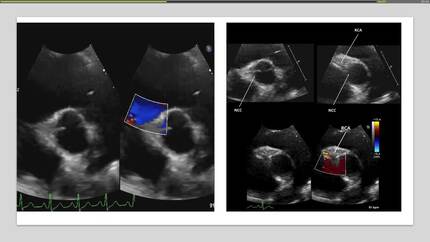

Anomalous origin of the right coronary artery from the pulmonary artery in a young girl